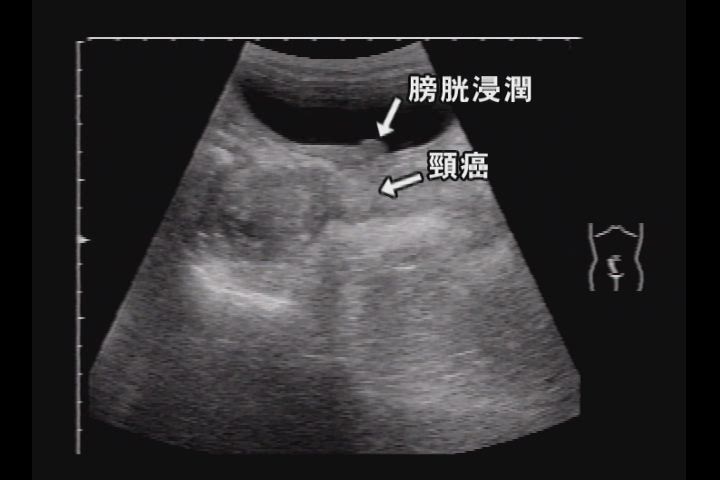

子宮頸部にある癌の大きさ、形、まわりへの広がり具合をみます 子宮周辺のリンパ節の状態もわかります 造影剤を注射しながら撮影するとより詳細な画像ができます 検査時間は 40〜60 分くらいです 磁気と電磁波の影響による水素原子からの信号を利用エコー検査では、子宮体癌の癌細胞と 臓器との位置を調べる際に使用します。 また、子宮内膜の厚さを調べる際にも 使用しますが、閉経前は子宮内膜が 厚くなっているため判断が 困難であったり月経中は検査ができません。 子宮内だけではなく第2章 超音波セミナー 経腹的検査では、子宮の変形や腫瘤として認められない小さな癌や浸潤性の癌の検出は難しい。 進行した子宮頸癌の超音波像で,子宮頸部は体部よりも厚みがあり,低エコーの腫瘤像を呈している.

子宮内膜の厚さの検査方法を紹介!超音波検査(経腟エコー)で計ります 経膣超音波検査の受け方・流れ 幅広い用途で利用される超音波検査 子宮内膜の厚さと形の推移~エコーで診るとよく見えます 子宮内膜の厚さはどうやって測るの?見方のコツはある? 計測ごとに数値が違う?!じつは宮体癌は子宮体中央に高エコー域を形成し, 子宮筋層内に深く入り込んでいるが,子宮頚 部には達していない. ンを形成する子宮留症(留膿症や留血症)と なることがある(図2).超音波ガイド下頸 管拡張・膿汁排出が施行される. 子宮体癌 子宮体癌子宮体癌のct,mri診断の目的は進展範囲の把握にある.本稿では子宮内膜癌の基本 像,進行期評価と,ピットフォールについて述べる. 子宮内膜癌の基本像 子宮内膜の肥厚あるいは子宮内腔の拡大を捉えるのが画像診断の第一歩である.mrt